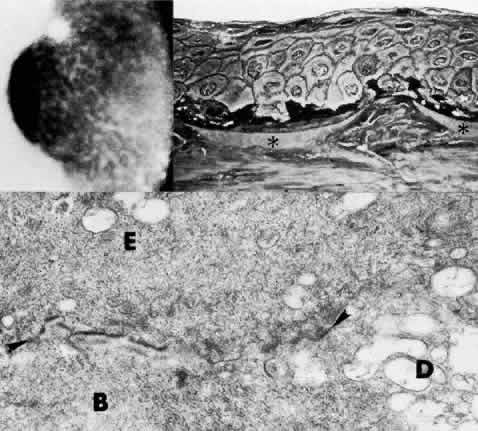

Central Crystalline Dystrophy (Schnyder)

This dominantly inherited dystrophy occurs in early life and is occasionally congenital (Figs. 5 AND 12).145–147 The main feature of the disease is a bilateral, axial, ring-shaped corneal opacity consisting of polychromatic crystals (Color Plate 1 I) .

Fig. 12. Central crystalline dystrophy (Schnyder). Top left. Clinical appearance of eye of 20-year-old woman includes ovoid crystalline deposit with clear surrounding stroma and without arcus lipidis. Visual acuity is 20/40. Bottom left. Light microscopy of cornea demonstrates epithelial irregularity and numerous crystalline profiles (circled) in Bowman's layer and stroma (toluidine blue, × 350). Right. Transmission electron micrograph demonstrates basal epithelium (E) with thickened basement membrane complexes (arrowhead), disorganized Bowman's layer (B), and polygonal crystalline profiles (*) typical of cholesterol. The keratocyte (K) is unremarkable (× 10,400). (Gipson I: Schnyder's crystalline dystrophy. Trans Am Ophthalmol Soc 76: 184, 1978)

The yellow-white opacity is noted in Bowman's layer and the anterior stroma. The epithelium is normal, and the uninvolved stroma also appears normal, although in time a diffuse stromal haze can develop. In some cases, small white opacities scattered throughout the stroma have been noted.148 Histologic examination using lipid stains on frozen sections reveals neutral fats and cholesterol.149 The clinically apparent crystals correspond to cholesterol accumulations, both within keratocytes and extracellularly. Neutral fat is distributed within the stroma among the collagen fibrils. Both the limbal girdle of Vogt and corneal arcus are associated with this dystrophy. The disease may be considered a localized defect of lipid metabolism, although some patients may also exhibit hypercholesterolemia, xanthelasma, and genu valgum. Because the disorder stabilizes with time, only occasional patients with severe opacity require corneal grafting.

It is important to perform cholesterol and lipid studies on these patients since, although the severity of a systemic lipid abnormality does not necessarily correlate with the severity of the corneal disease, elevated serum lipid levels and concomitant cardiovascular disease are associated features in some patients.150